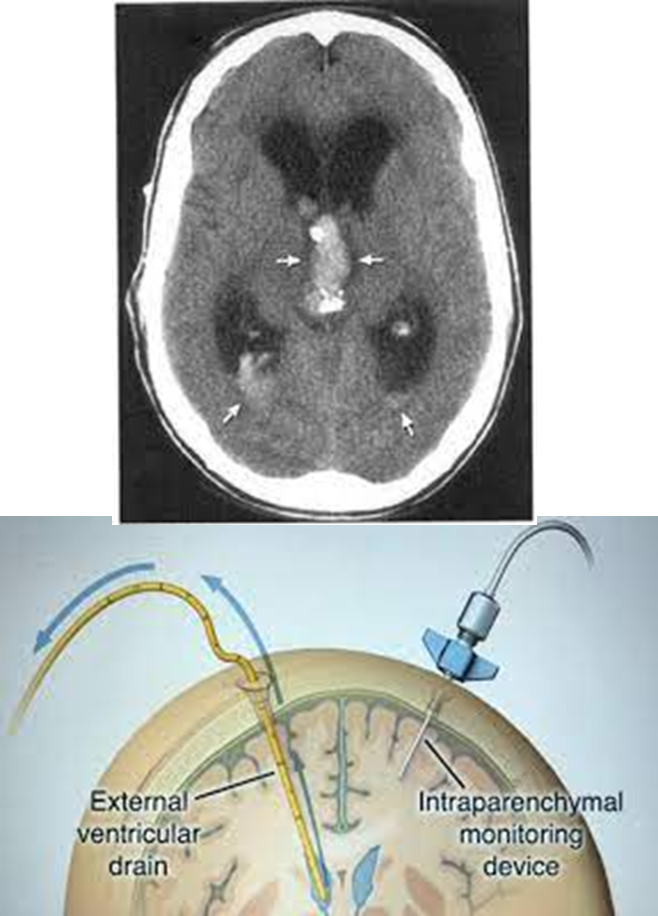

How is Non-communicating hydrocephalus treated?

Patients with obstructive or non-communicating hydrocephalus are treated with the placement of an external ventricular drain

→ often occurs in patients with extension of hemorrhage into a ventricle